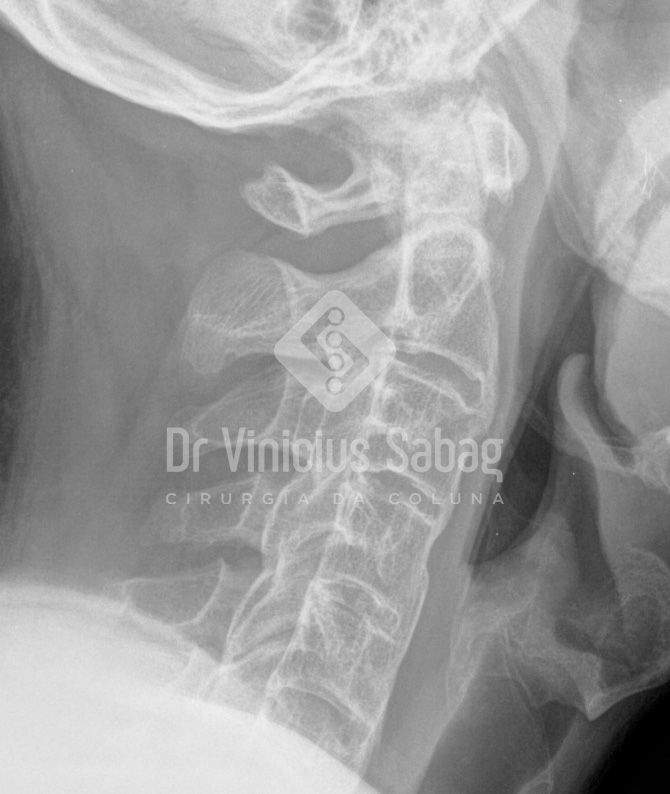

Raio X evidenciando ossificação entre as vértebras da coluna cervical.

Na espondilite anquilosante, a inflamação contínua pode causar alterações estruturais nas articulações da coluna. Com o passar do tempo, o organismo tenta “cicatrizar” essas áreas inflamadas produzindo novo osso, o que pode resultar na fusão de vértebras — processo conhecido como anquilose. Essa fusão reduz a flexibilidade da coluna e pode levar a uma postura encurvada, com impacto direto na qualidade de vida.